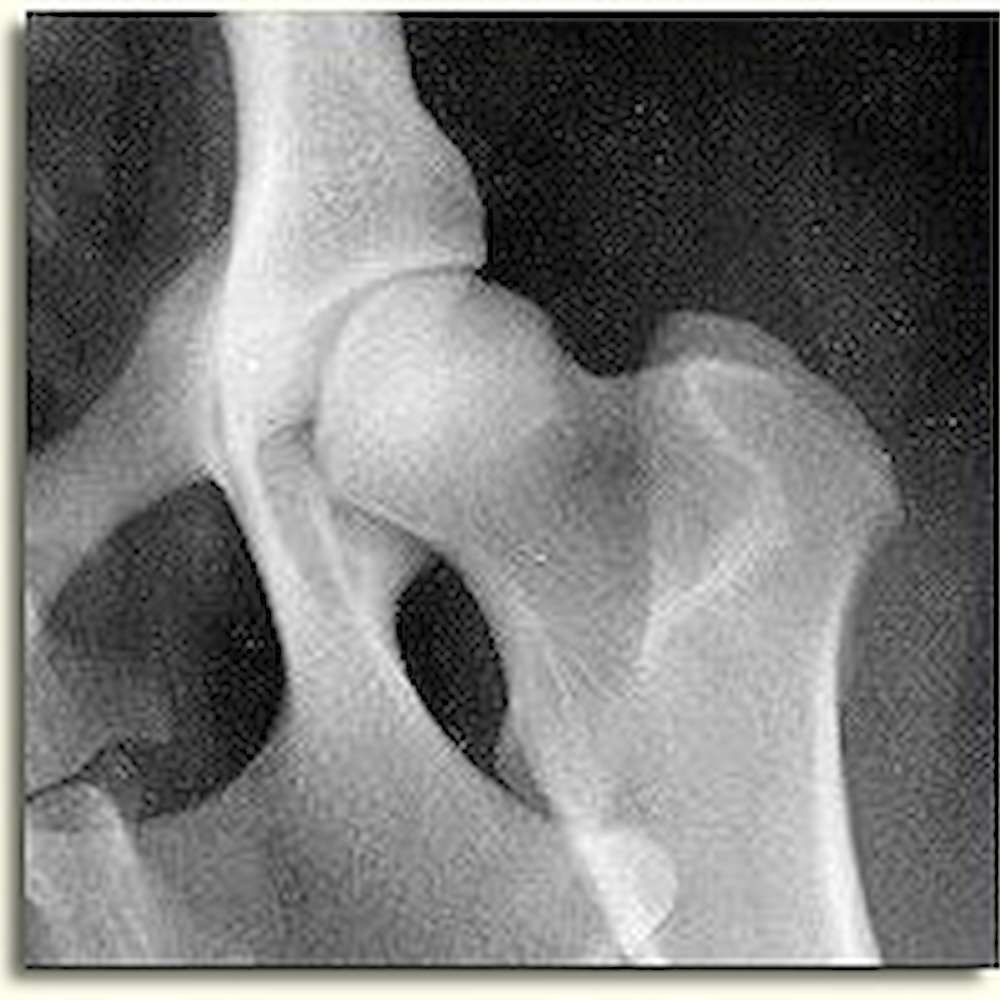

Luxation means dislocation. A luxated hip is one that has extreme laxity such that it displays dislocation of the two bones of the joint. The x-ray image at the top right of this page demonstrates a fully luxated hip on the right side of the image.

Subluxation means a partial dislocation of two joint members. The x-ray image at the top right of this page demonstrates a subluxated hip on the left side of the image.